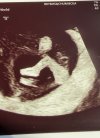

Hejka:) wczorajsza wizyta mnie bardzo uspokoiła wszystko jest ok:) potem byłam

na prenatalnych i teraz czekam z niecierpliwością na wyniki i usg prenatalne☺️ A dzisiaj dostałam takiego powera, że nagotowałam, psie fryzury ogarnęłam i polatałam po lesie 10 km jak przed ciążą bez zadyszki🥰